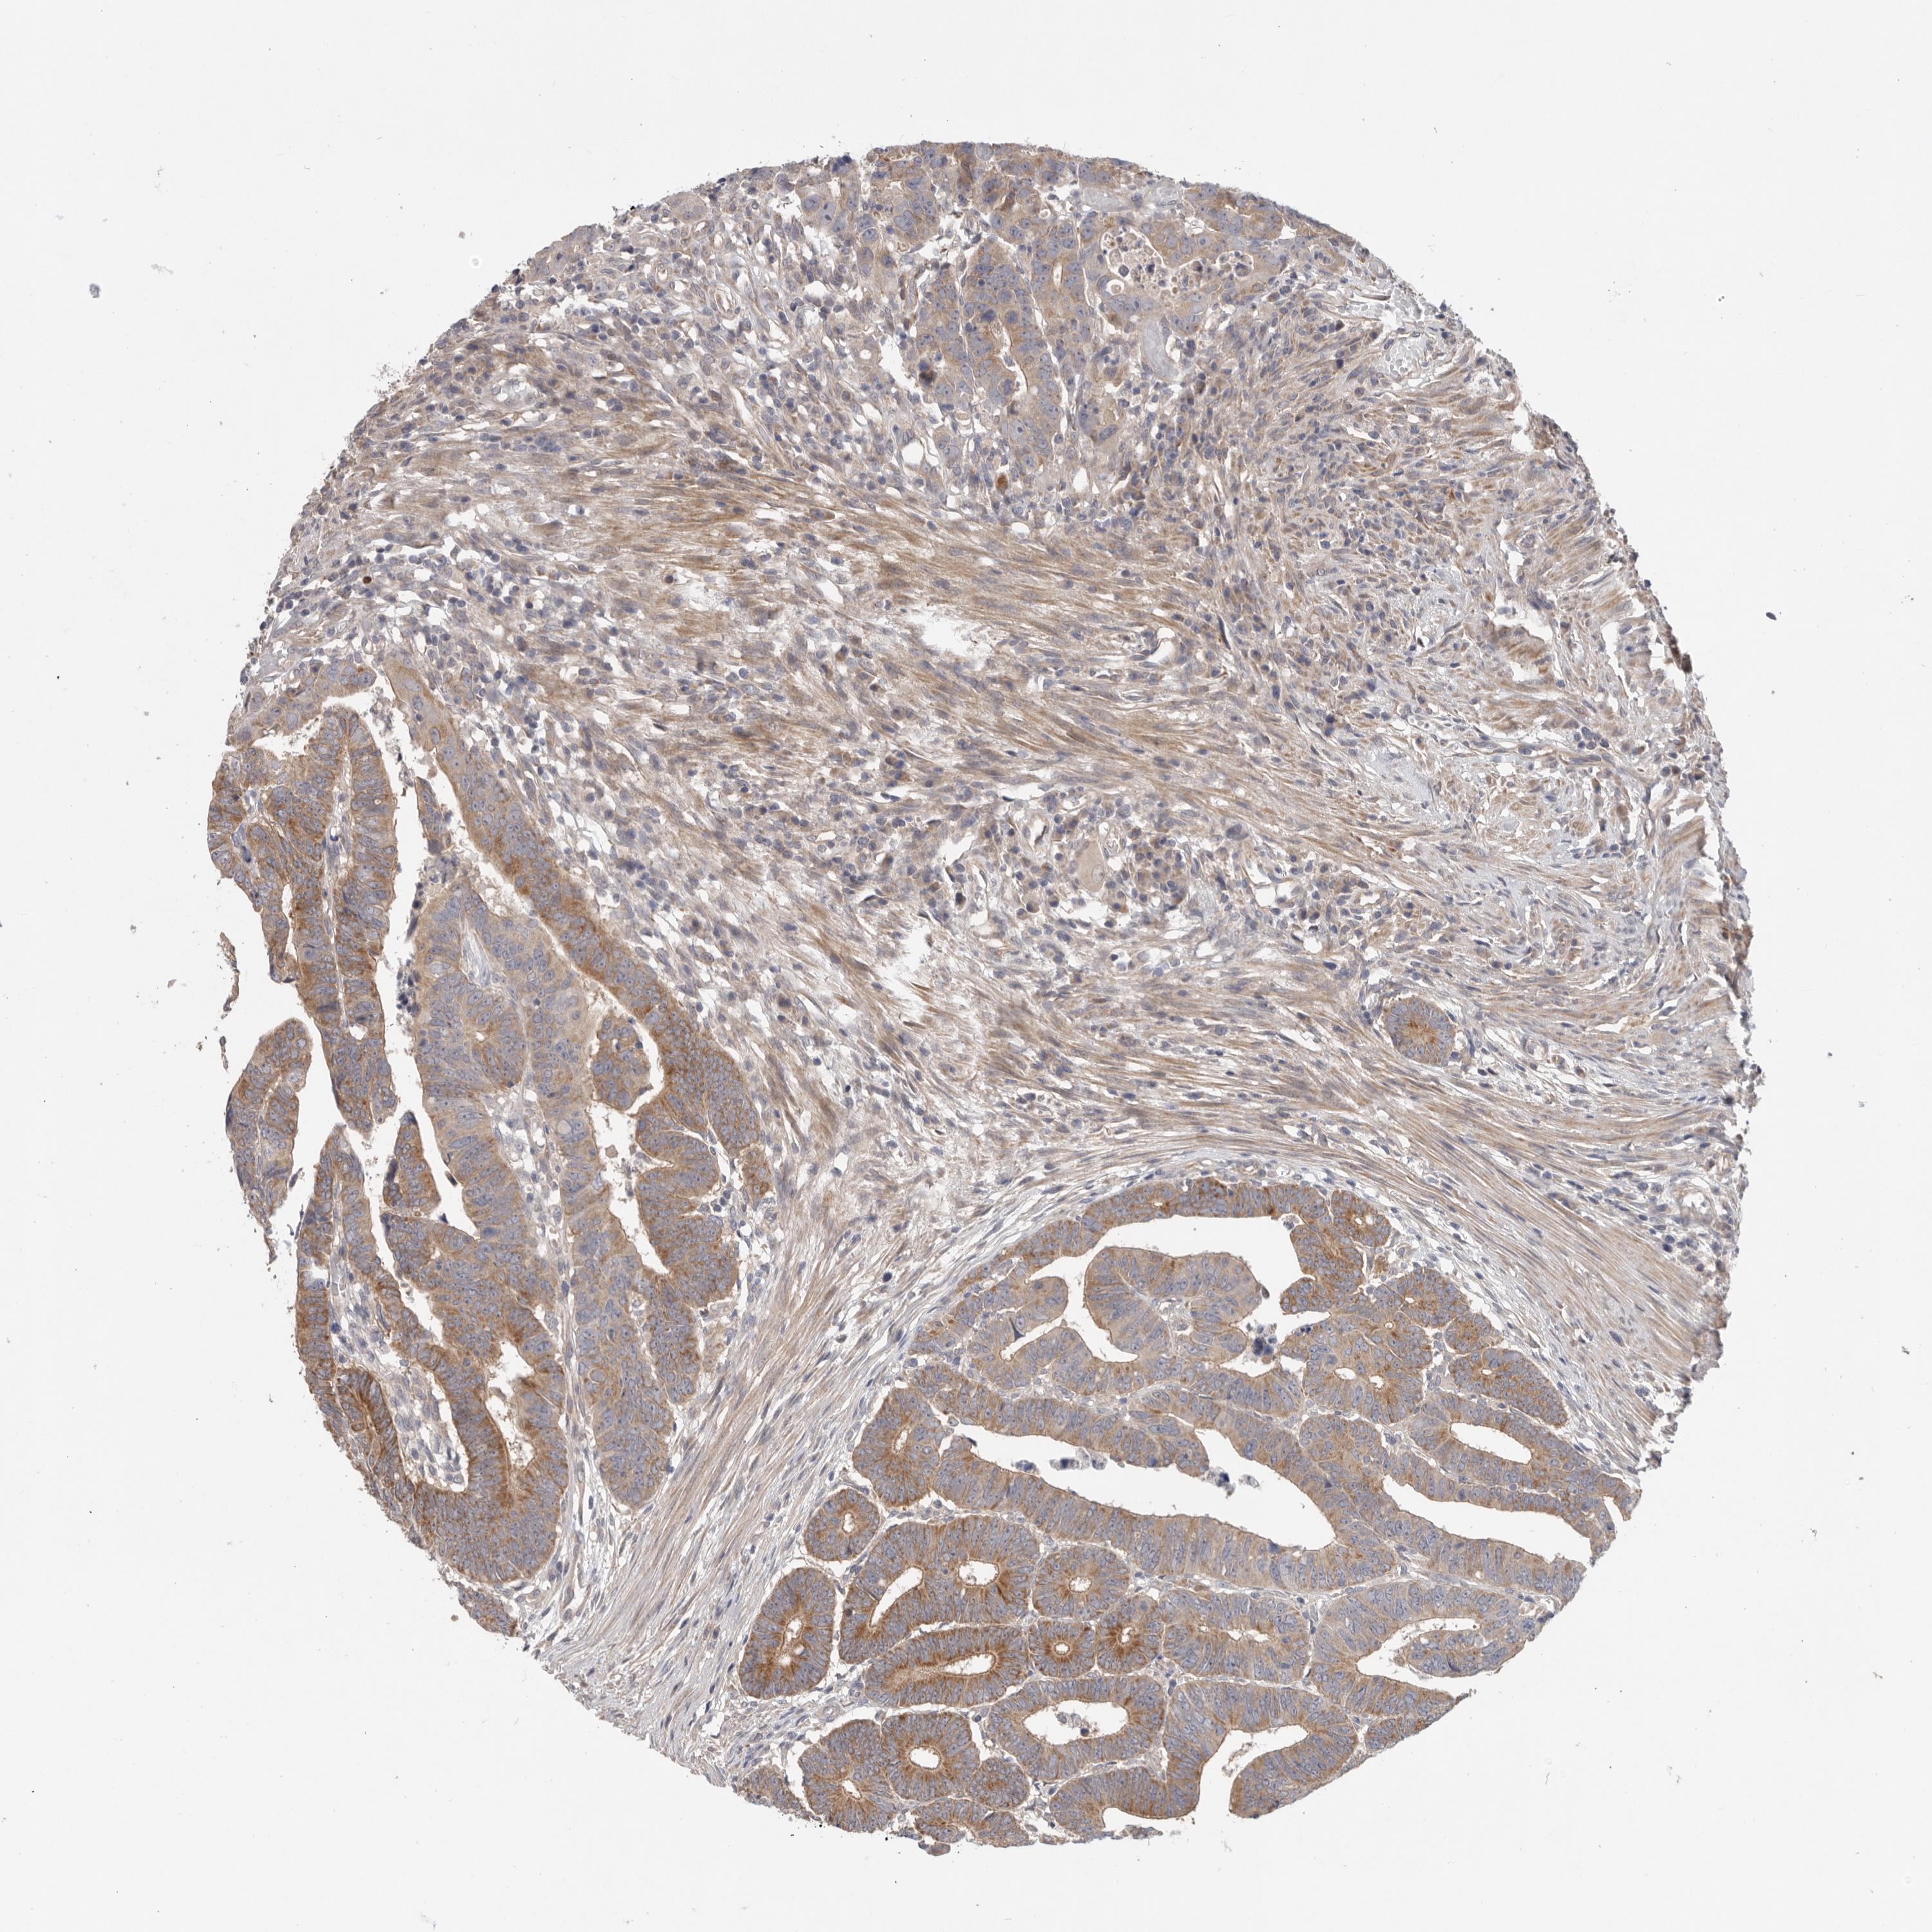

CANCER COLORECTAL CANCER Show tissue menu

Colorectal cancer

Human cancer

Colon adenocarcinoma